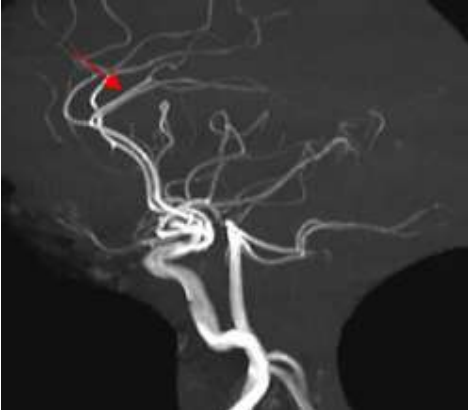

Paciente de 7 anos, sexo feminino, é atendida em unidade de urgência com episódios recorrentes de cefaleia e déficit motor dimidiado temporário. Em investigação complementar realiza estudo angiográfico que demonstra os achados de imagem abaixo.

Baseado no caso e nas imagens apresentadas, assinale a alternativa correta.